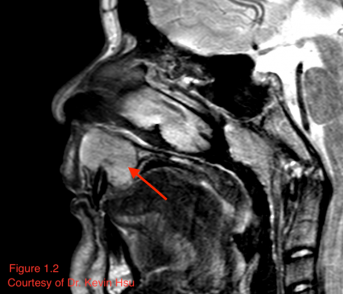

CT usually reveals a well-defined, heterogeneously enhancing mass with areas of fine and coarse calcification (Font 2009).[14] Such radiologic appearance is considered characteristic, and internal calcifications in particular should raise concern for possible mesenchymal chondrosarcoma (Angotti-neto 2006, Koeller 1999).[15][16] However, not all tumors will demonstrate such calcification (Lu 2009).[17] The lesion tends to have the same attenuation as muscle (Murphey 2003)[8], and generally, the radiopaque areas correlate with areas of high-grade sarcoma and hemangiopericytoma while radiolucent portions correspond to the areas of chondrosarcoma (Font 2009).[14] Figure 1.1 illustrates a case of orbital mesenchymal chondrosarcoma in which the CT revealed a homogenous isodense mass with the same attenuation as muscle and no areas of calcification. Although the lesion appeared non-specific on CT, the diagnosis was confirmed by histopathology after resection.